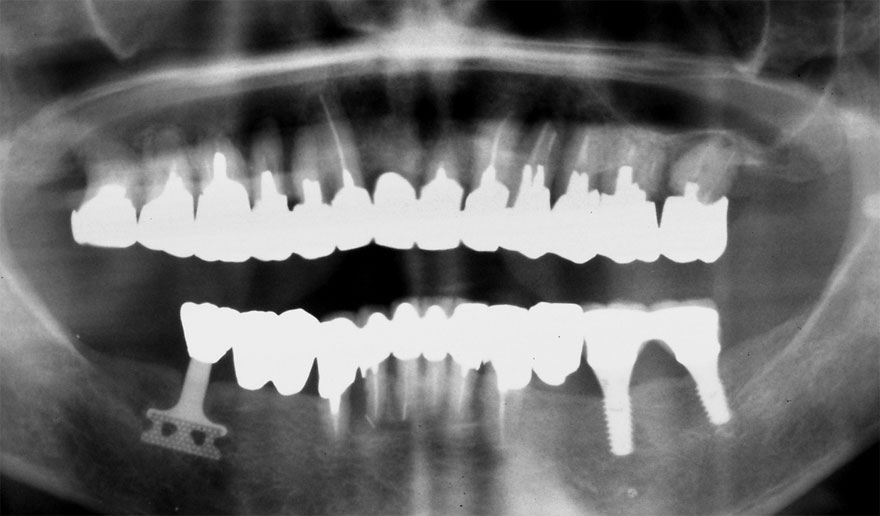

初診時 50歳 男性

30年後 80歳